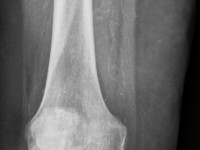

Calciphylaxis cutisCalciphylaxis cutis is een zeldzame aandoening

waarbij grillige en zeer pijnlijke ulcera ontstaan door

calciumdeposities in

kleine en medium-size arteriën. De kalkafzettingen kunnen in een huidbiopt

worden gezien in en ook rond de vaten in de dermis en subcutis. Op

röntgenfoto's is vaak uitgebreide verkalking te zien: het complete arteriële

stelsel is verkalkt en zichtbaar, alsof het een contrastfoto was. De huid

die werd voorzien door het afgesloten arterietakje sterft af, hierdoor is de

aandoening zeer pijnlijk. De prognose is slecht en de sterfte is hoog, omdat

er niet alleen huidinfarcten ontstaan maar ook infarcten elders in het

lichaam (hartinfarct, herseninfarct, necrose van de darm na infarct in de a.

mesenterialis). De klassieke calciphylaxis cutis wordt gezien bij patiënten

met (meestal langdurige bestaande)

terminale nierinsufficiëntie en

secundaire hyperparathyreoïdie. Vooral bij dialyse patiënten. Waarschijnlijk

![Calciphylaxis cutis bij nierinsufficiëntie en secundaire hyperparathyreoïdie (click on photo to enlarge) [source: www.huidziekten.nl] Calciphylaxis cutis bij nierinsufficiëntie en secundaire hyperparathyreoïdie](../../../images/calciphylaxis-1z.jpg) |

![Calciphylaxis cutis bij nierinsufficiëntie en secundaire hyperparathyreoïdie (click on photo to enlarge) [source: www.huidziekten.nl] Calciphylaxis cutis bij nierinsufficiëntie en secundaire hyperparathyreoïdie](../../../images/calciphylaxis-2z.jpg) |

| calciphylaxis cutis |

calciphylaxis cutis |